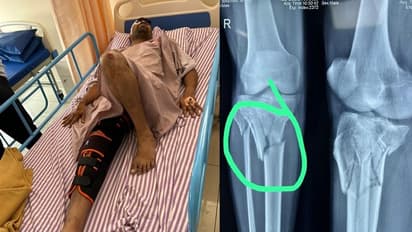

ಬೆಂಗಳೂರು(ಮೇ.24): ಬೆಂಗಳೂರಲ್ಲಿ ಸುರಿದ ಒಂದು ಮಳೆಗೆ ನಗರದಲ್ಲಿನ ಅವಾಂತರಗಳು ಹೊರಬಂದಿದೆ. ಅವೈಜ್ಞಾನಿಕ ಕಾಮಗಾರಿಗಳು, ನೀರು ಹರಿಯಲು ಜಾಗವಿಲ್ಲದೆ ಕೆರೆಯಂತಾಗುವ ರಸ್ತೆಗಳು ಸೇರಿದಂತೆ ಸಮಸ್ಯೆಗಳ ತುಂಬಿ ಹೋಗಿದೆ. ಇದು (Bengaluru Rain) ಮಳೆ ಹಾಗೂ ಮಳೆನೀರಿನ ವಿಚಾರವಾದರೆ, ಇತ್ತ ಬಿಬಿಎಂಪಿಯ(BBMP) ಮರಳಗಳ ಕಳಪೆ ನಿರ್ವಹಣೆಯಿಂದ ಈಗಾಗಲೇ ಹಲವು ದುರಂತಗಳು ಸಂಭವಿಸಿದೆ. ಇದೀಗ ಬಿಬಿಎಂಪಿ ನಿರ್ಲಕ್ಷ್ಯಕ್ಕೆ ಜೆಪಿ ನಗರ ನಿವಾಸಿ ಶ್ರೀಧರ್(36) ಕಾಲು ಮುರಿತ ಹಾಗೂ ತಲೆಗೆ ಗಂಭೀರ ಗಾಯಗೊಂಡು ಆಸ್ಪತ್ರೆ ಸೇರಿದ್ದಾರೆ. ಸ್ಕೂಟರ್ ಮೂಲಕ ಕೆಲಸಕ್ಕೆ ತೆರಳುತ್ತಿದ್ದ ವೇಳೆ ಮರದ ಕೊಂಬೆಯೊಂದು ಮುರಿದು ಬಿದ್ದಿದೆ. ಇದರಿಂದ ವ್ಯಕ್ತಿಯ ಕಾಲಿನ ಮೂಳೆಗಳು ಮುರಿತಕ್ಕೊಳಗಾಗಿದೆ. ತಲೆಗೆ ಗಂಭೀರ ಗಾಯವಾಗಿದೆ.

ಟೈಲ್ಸ್ ಶೋ ರೂಂನಲ್ಲಿ ಅಕೌಟೆಂಟ್ ಆಗಿರುವ ಶ್ರೀಧರ್, ಬೆಳಗ್ಗೆ 10 ಗಂಟೆಗೆ ಕೆಲಸಕ್ಕೆ ತೆರಳುತ್ತಿದ್ದ ವೇಳೆ ಈ ಘಟನೆ ನಡೆದಿದೆ. ಮುರಿದ ಕೊಂಬೆ ನೇರವಾಗಿ ಸ್ಕೂಟರ್ನಲ್ಲಿ ಸಾಗುತ್ತಿದ್ದ ವ್ಯಕ್ತಿಯ ಮೇಲೆ ಬಿದ್ದಿದೆ. ತಕ್ಷಣವೇ ಶ್ರೀಧರ್ ಅವರನ್ನು ಜೆಪಿ ನಗರದ ಖಾಸಗಿ ಆಸ್ಪತ್ರೆಯಲ್ಲಿ ದಾಖಲಿಸಲಾಗಿದೆ. ಇತ್ತ ಬಿಬಿಎಂಪಿ ಈ ಘಟನೆ ಕುರಿತು ಮೌನ ವಹಿಸಿದೆ. ಶ್ರೀಧರ್ ಕಾಲು ಸಂಪೂರ್ಣ ಮುರಿದು, ಗಂಭೀರವಾಗಿ ಗಾಯಗೊಂಡಿರುವ ಕಾರಣ ಸುದೀರ್ಘ ಕಾಲದ ವಿಶ್ರಾಂತಿ ಅಗತ್ಯವಿದೆ. ಇತ್ತ ಕುಟುಂಬಕ್ಕೆ ಆಧಾರವಾಗಿದ್ದ ಶ್ರೀಧರ್ ಆಸ್ಪತ್ರೆ, ವೆಚ್ಚ ಕುಟುಂಬದ ನಿರ್ವಹಣೆಗೆ ದಿಕ್ಕೆ ತೋಚದಾಗಿದೆ.